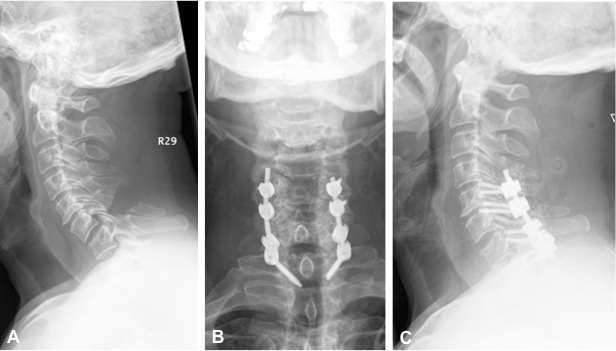

A New Transpedicular Lag Screw Fixation For Treatment Of Unstable Hangman S Fracture A Minimum 2 Year Follow Up Study Journal Of Orthopaedic Surgery And Research Full Text

The Surgical Management Of Traumatic Lower Cervical Spondylolisthesis With Posterior Percutaneous Pedicle Screw Fixation